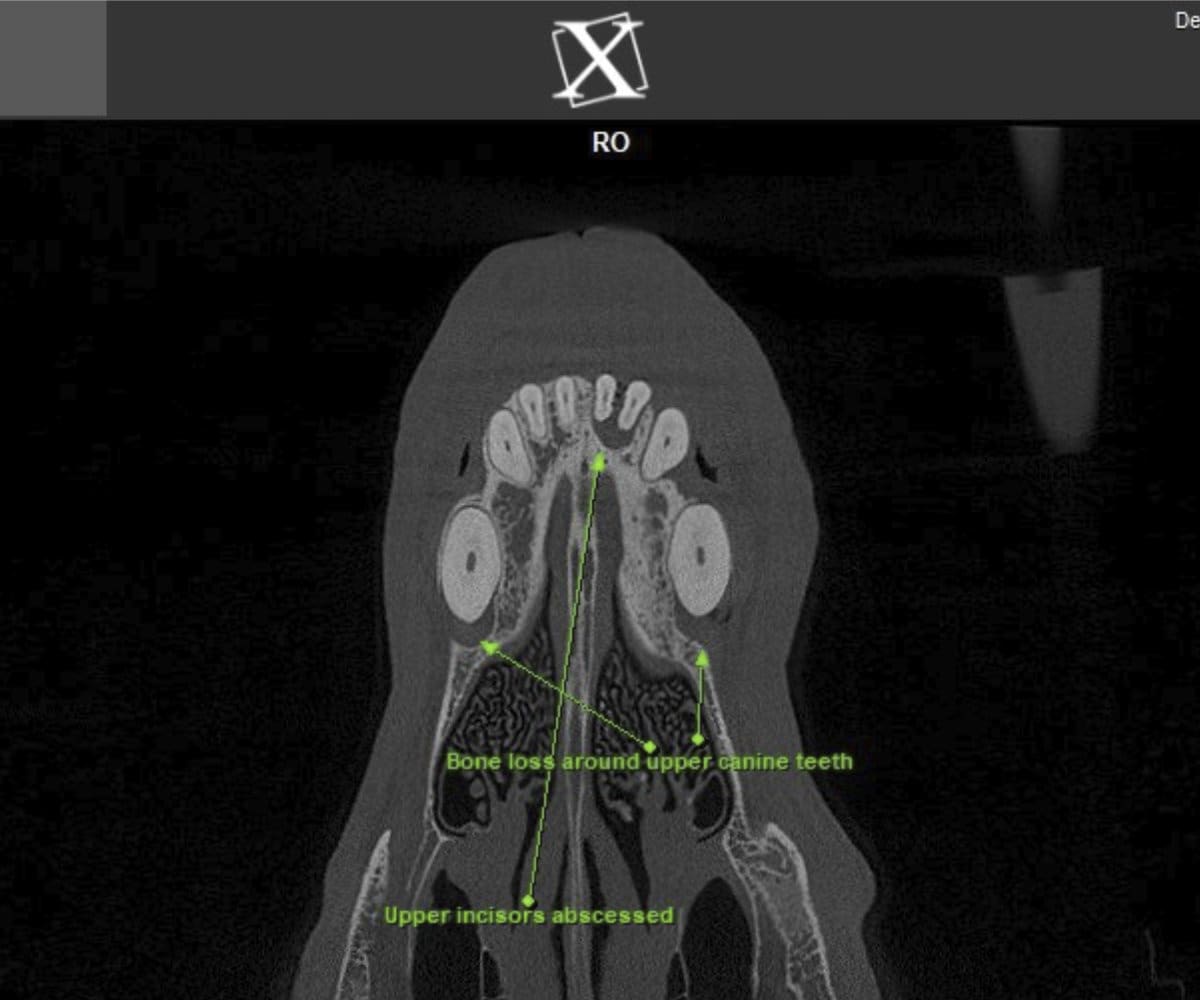

In addressing these limitations, CBCT emerges as a pivotal advancement. Conducting a CBCT scan on our patients is characterized by minimal time and effort, effectively reducing anesthesia duration. Moreover, this technology facilitates the generation of a comprehensive 3D reconstruction of the teeth and skull, surpassing the constraints of traditional radiographs. This innovative approach empowers our veterinary professionals to identify oral pathologies that may have been missed on traditional radiographs.

Cone beam CT technology provides veterinarians with 3-dimensional images in far greater detail than dental radiographs. CBCT scans significantly decrease the amount of time a patient spends under anesthesia compared to the time it takes to complete dental radiographs.

Our CBCT VetCAT unit is easily rolled up to our treatment table and takes only 40 seconds to complete a scan. It has proven to be invaluable in the diagnosis and treatment planning for pets with periodontal, endodontic and cancerous disease conditions. It is also indispensable in the evaluating our trauma cases with jaw fractures.